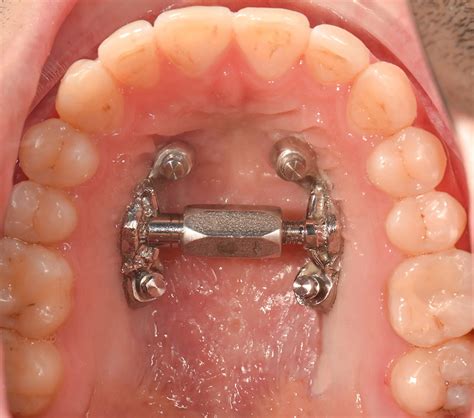

- Disyuntores: Se apoyan normalmente en los dientes y poseen un tornillo de expansión que se va girando poco a poco para ir ensanchando el maxilar. Normalmente se hace una primera etapa de activación del tornillo del aparato, donde se le van dando vueltas progresivamente al tornillo; y luego otra fase de retención, en la que se mantiene su uso para que se consolide el resultado.

Expansión Rápida del Maxilar (ERM)

La denominada expansión rápida del maxilar o disyunción, es el mejor ejemplo de la verdadera expansión de tipo ortopédico, ya que los cambios son producidos principalmente en las estructuras óseas subyacentes, en vez de por el movimiento dentario a través del hueso alveolar.

La expansión rápida del maxilar, provoca la separación de la sutura media palatina y además afecta a los sistemas suturales circuncigomáticos y circunmaxilares.